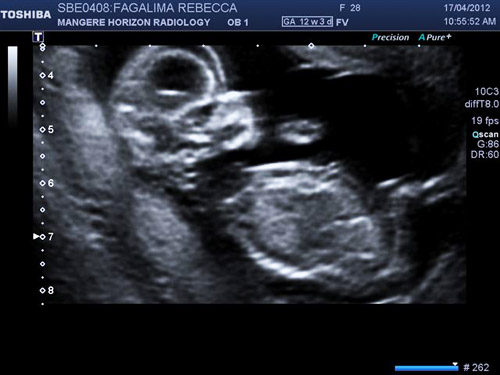

All of the radiology clinics were busy, our scan date got pushed out to closer to 13 weeks however reaching that 12 week mark without any significant events my husband and I felt "safe" to share the news and scream from the rooftops we had a bundle of joy on the way. At our scan we could see our precius bundle bouncing around, sucking her thumb and waving to us. As the sonographer continued things got silent. The silence I will never ever forget, then she broke it with the news no parent ever wants to hear. Our baby had something wrong, her nuchal measurement was extremely high (off the chart high) and her lungs weren't forming and they should, and that was it. We were left to up and leave and go away with no further answers. I walked out the door crying, no actually bawling. What was wrong with my baby, why had this happened to me. We had to wait for a specialist appointment for any details.